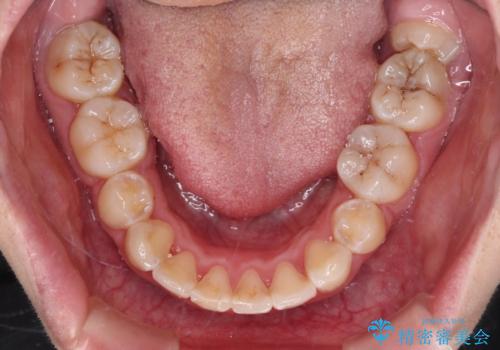

- 骨格的な咬み合わせのズレ、前歯のデコボコとクロスバイトを気にして来院された患者様です。

口元の突出感が若干あり口が閉じにくく、デコボコが強いため、上下左右の小臼歯計4歯を抜歯し、ワイヤー装置による矯正治療を行うこととしました。

また、舌の突出癖が強く、下顎前歯が前方に押し広げられる可能性が高いため、舌癖の改善を継続的に行うよう指示しました。